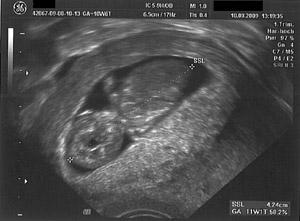

Hallihallo, oh man endlich kann ich auch mal ein Bildchen online stellen! Unser scanner @ home ist kaputt und nun habe ich es meinem Freund mit auf arbeit gegeben! Das ist vom 10.08., da war ich in 10 + 6. Baby ist schon 4,24 cm groß! Ich find das Bild total süß und freue mich voll.. Schöne Kugelzeit an alle! VG Kiki

Bild zu US-Bildchen - Forum für März - Mamis